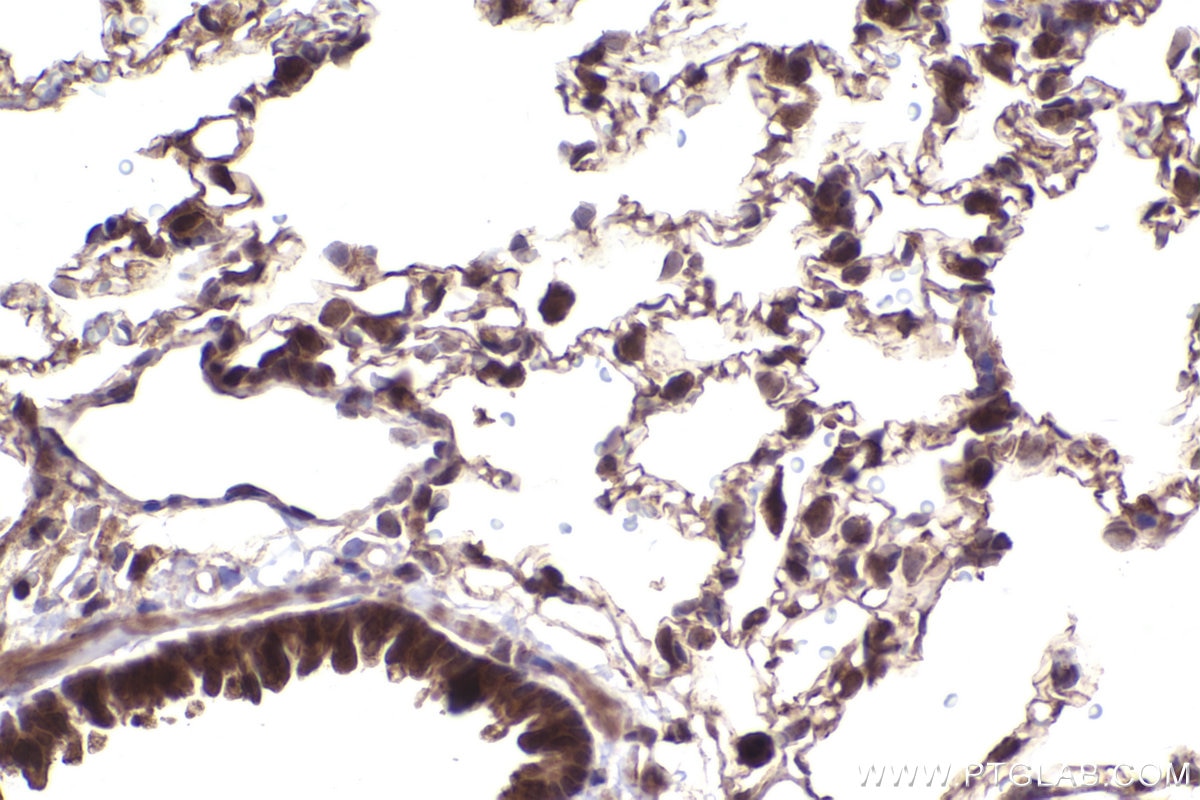

IHCeasy® NFE2L2/NRF2 Ready-To-Use IHC Kit

NFE2L2/NRF2 Ready-to-use reagent kit for IHC.

KHC2502 is a ready-to-use IHC kit for staining of NFE2L2/NRF2. The kit provides all reagents, from antigen retrieval to cover slip mounting, that require little to no diluting or handling prior to use. Simply apply the reagents to your sample slide according to the protocol and you're steps away from obtaining high-quality IHC data.

NRF2, also named as NFE2L2, belongs to the bZIP family and CNC subfamily. It is a transcription activator that binds to antioxidant response (ARE) elements in the promoter regions of target genes. NRF2 is important for the coordinated up-regulation of genes in response to oxidative stress. It may be involved in the transcriptional activation of genes of the beta-globin cluster by mediating enhancer activity of hypersensitive site 2 of the beta-globin locus control region. Nrf2 is a key player in the regulation of genes encoding for many antioxidative response enzymes. The expression of NRF2 may be induced under oxidative stress. In lung cancer, Nrf2 activation in malignant cells has been associated with tumor progression and chemotherapy resistance. Identifying patients with abnormal NRF2 expression may be important for selection for chemotherapy in NSCLC.